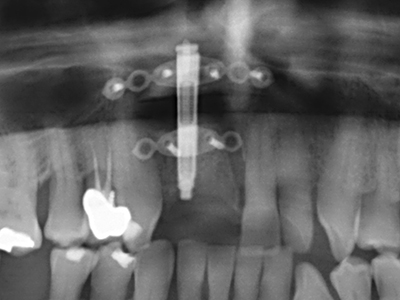

Die Präparation des lateralen Fensters bei der externen Sinusbodenelevation stellt gerade für chirurgisch unerfahrene Implantologen eine große Herausforderung dar. Die knöcherne Bedeckung der Kieferhöhle ohne eine Verletzung der darunterliegenden Schneider’schen Membran abzutragen ist dabei nur ein Teil der Operation – nach Schaffung eines ausreichenden Zugangs muss die Kieferhöhlenschleimhaut vorsichtig mobilisiert werden, um Raum für das einzubringende Material bzw. die Implantate zu schaffen. In dieser Indikation ist die Piezochirurgie zweierlei hilfreich: zum einen kann durch Verwendung diamantierter Instrumente eine selektive Knochenabtragung erfolgen und die darunter liegende Schleimhaut bleibt bei vorsichtiger Vorgehensweise intakt. Zum anderen unterstützen die Ultraschallfrequenzen zusätzlich eine komplikationslose Ablösung der Schleimhaut – sie werden durch spezielle stumpfe Ansätze in den Spaltraum zwischen Schleimhaut und Kieferhöhlenboden übertragen (Cassetta, Ricci et al. 2012, Pereira, Gealh et al. 2014) (Rickert, Vissink et al. 2013). So erscheint es nicht verwunderlich, dass in aktuellen Übersichtsarbeiten über die externe Sinusbodenelevation neben der Verwendung von rauen Implantatoberflächen und dem Einsatz von Knochenersatzmaterialien auch der Einsatz von piezoelektronischen Geräten als positiv bewertet wird (Wallace, Tarnow et al. 2012).

Wie sich in der Vergangenheit gezeigt hat stellt prinzipiell jeder knochenchirurgische Eingriff eine mögliche Indikation für die Piezochirurgie dar. So lässt sich die Präparation des mobilen Segmentes bei der Distraktionsosteogenese (Abb. 23-25) und der Sandwichosteotomie mit speziellen Ansätzen bewerkstelligen, ohne die für den Erfolg beider Techniken essenzielle Blutversorgung des krestalen Anteils zu gefährden (Gonzalez-Garcia, Diniz-Freitas et al. 2008).

Für die Entnahme von Implantaten ist die Präparation eines vestibulären Knochendeckels möglich, der nach Entfernung der Implantatschraube refixiert wird und auf diesem Wege die Kontur des Alveolarfortsatzes erhält.

Weitere Einsatzgebiete ergeben sich in der Kieferhöhlenchirurgie: Hier können nach konzentrischer Präparation eines in der Regel trapezförmigen Knochendeckels der fazialen Kieferhöhlenwand Pathologien und Fremdkörper aus der Kieferhöhle entfernt werden. Der Knochendeckel wird nach Abschluss des intra-antralen Operationsanteils reponiert und durch Verkeilen oder adaptierende Nähte gegen Dislokation gesichert.